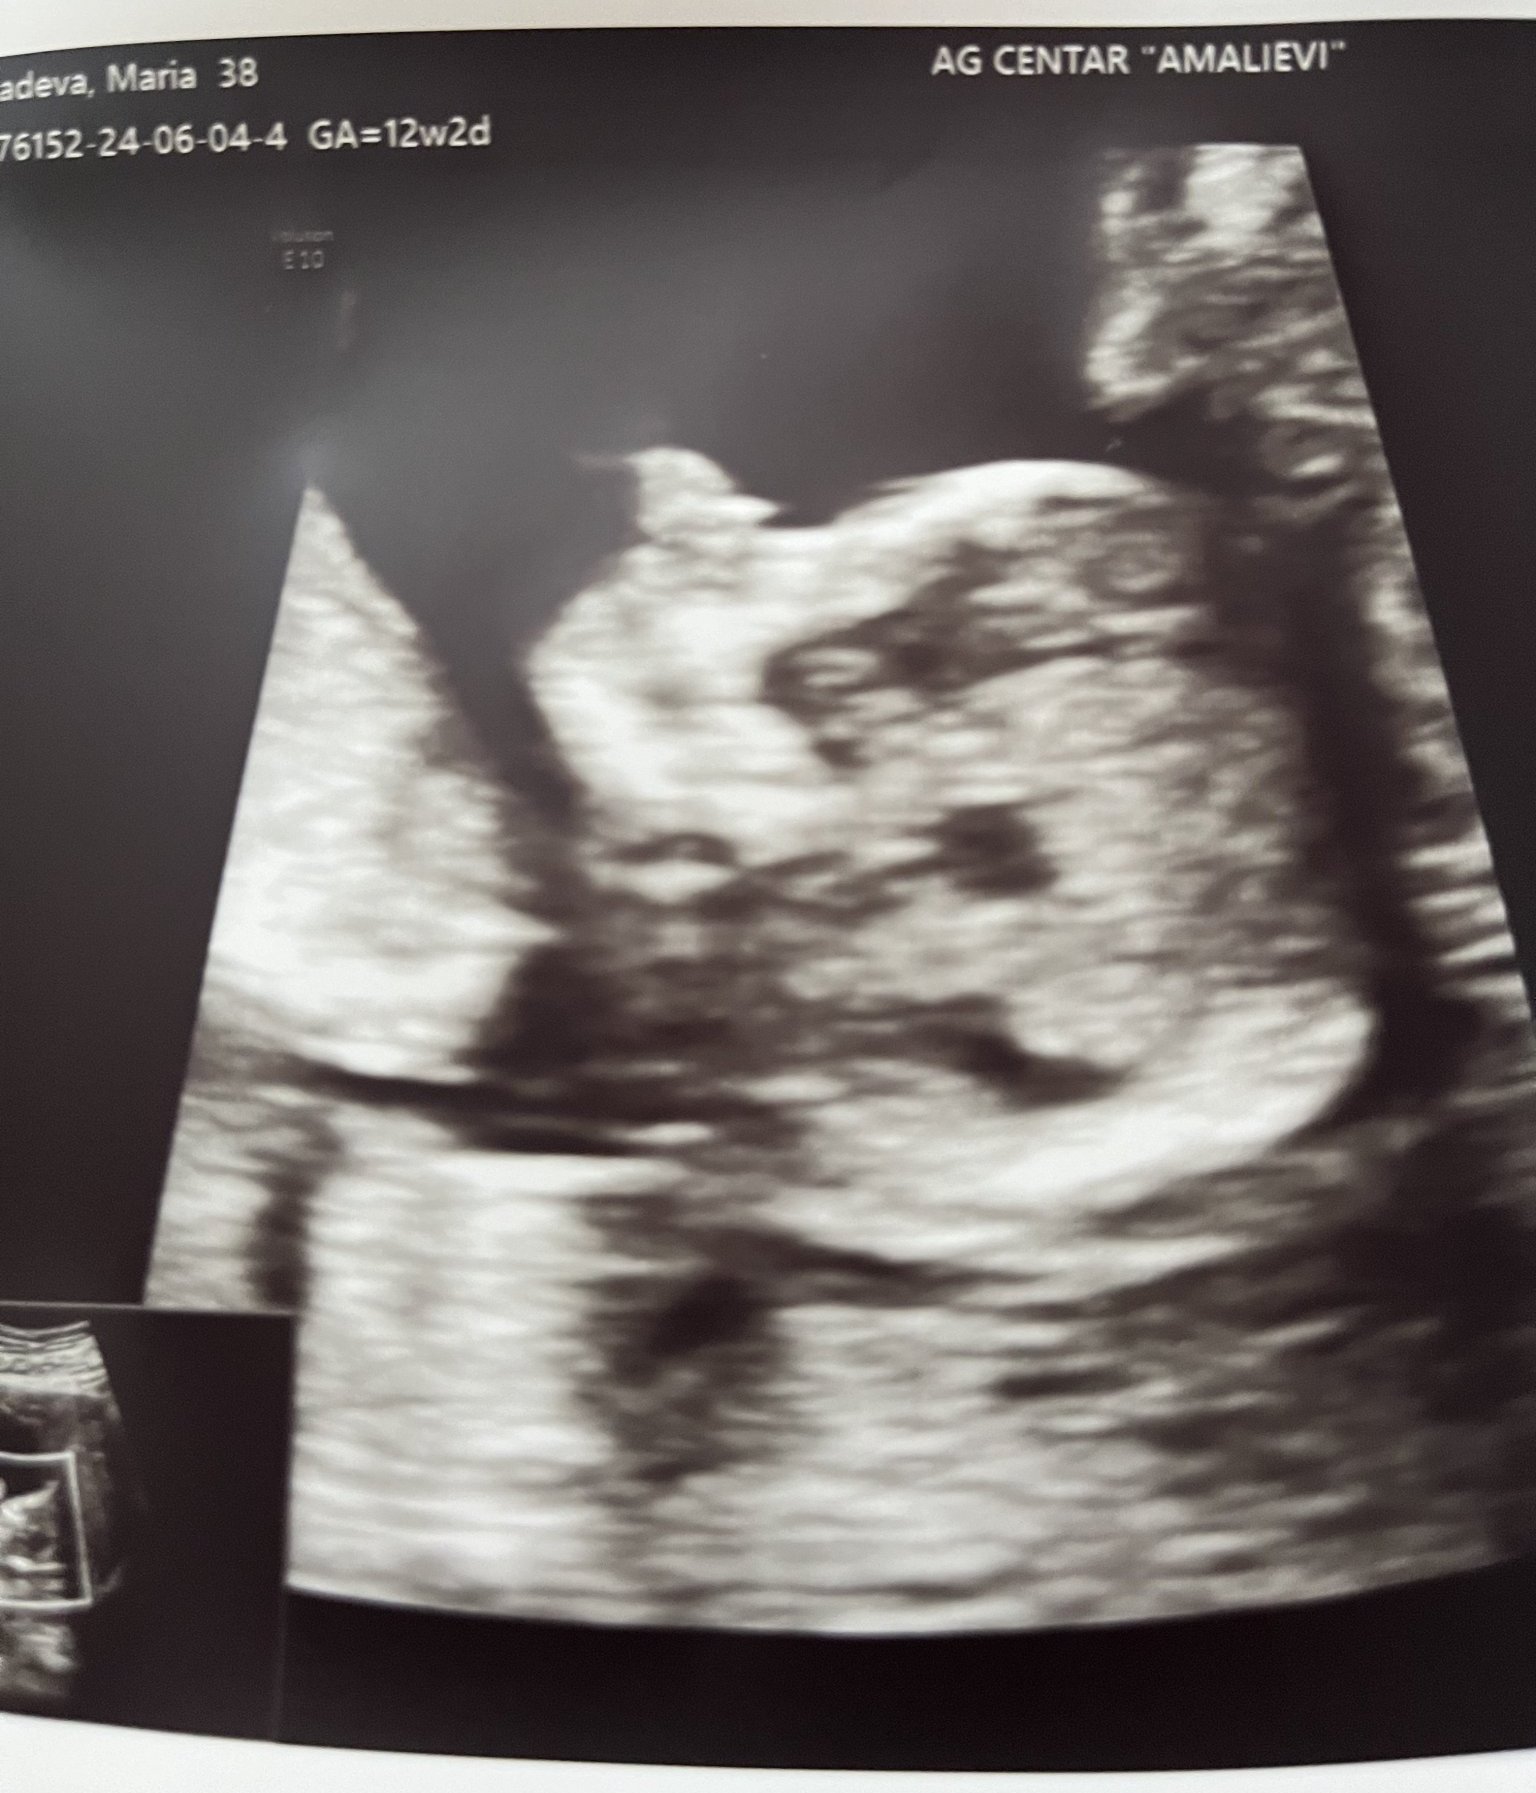

• Мнения: 68

Здравейте ъпдейт от мен вчера бях на преглед 13+4 потвърди се че ще е момиченце вече е 7см. И тежи 70 грама всичко е наред с бебето и вече определено си усещам ритниците вчера споделих и на лекарката и тя ми каза че е нормално за втора бременност особено след като съм усетила и каката доста рано и двата пъти съм с предна плацента. И за цялото тримесечие съм качила само 800гр. За което се радвам😁